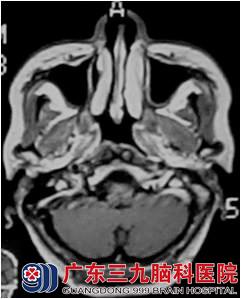

龚小姐于2012年9月因“右颈肿物3年余”,外院活检病理示:鼻咽未分化型非角化性癌。查体:右颈II区淋巴结约26mm X 15mm,边界尚清。9月12日胸部DR未见异常未见骨转移及身体其他部位转移征象,为进一步治疗,于10月份和11月份来广东三九脑科医院肿瘤综合治疗中心行鼻咽癌适形调强放疗,放疗50Gy/25f后复查鼻咽MR示鼻咽病变及颈部淋巴结影基本消失。7000cgy/35f,双颈部放疗5000cgy/25f,右上颈部推量至6000cgy/30f,放疗顺利放疗后行4周期低毒性化疗。

治疗过程很顺利,目前治疗后近2年,复查鼻咽MR:1.鼻咽癌放疗后改变,目前鼻咽部未见明确肿瘤复发征象;2.原右侧颈部颈动脉鞘旁稍大淋巴结已消失。